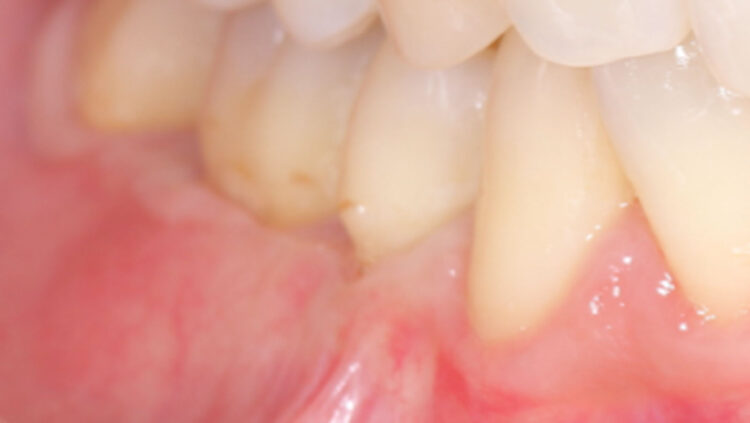

- 【術後】奥歯の歯肉退縮症例②